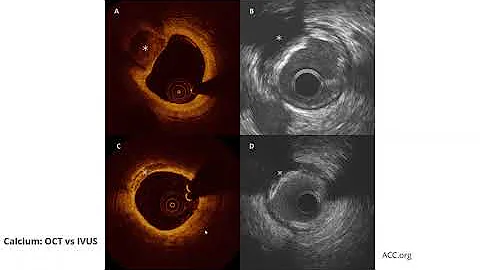

The Comparative Role Of Oct, Ivus And Ffr In Cad Assessment (colin M. Barker, Md)